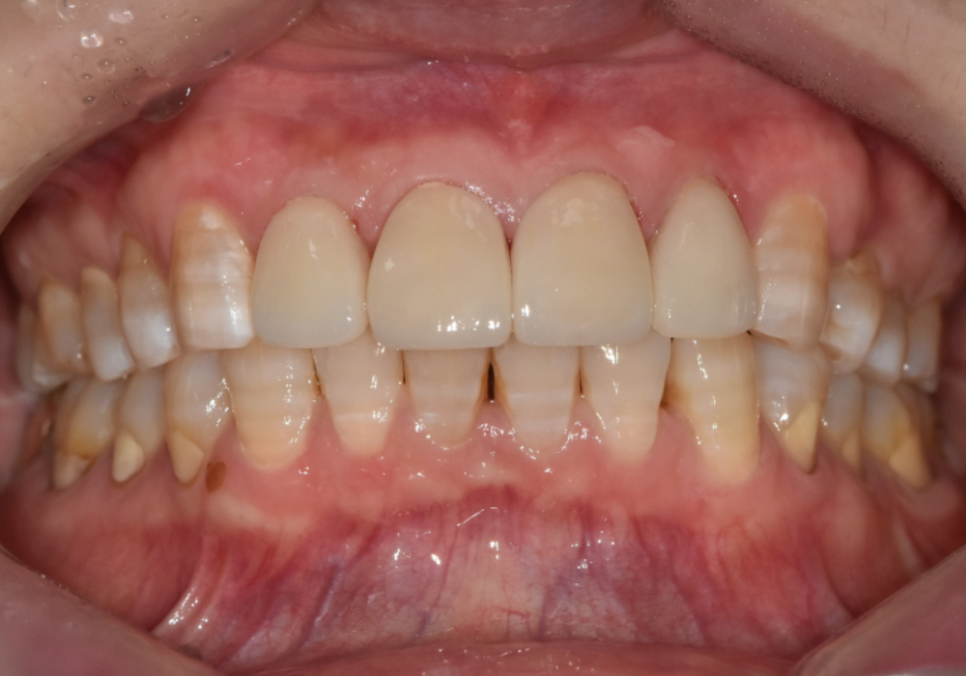

치아 벌어짐을 자연스럽게 메우면서도

치아가 너무 커 보이지 않도록

크기와 비율을 꼼꼼하게 맞춰 드렸습니다.

색상은 환자분이 원하시는 밝기 범위 안에서,

자연스럽고 건강해 보이도록 제작했습니다.

완성 후에는 갈색 가로줄도 보이지 않게 되었고,

치아 색도 밝고 균일하게 정돈됐습니다.

250307

치아 벌어짐도 자연스럽게 메워져서

웃을 때 자신감이 생겼다고 하셨습니다.